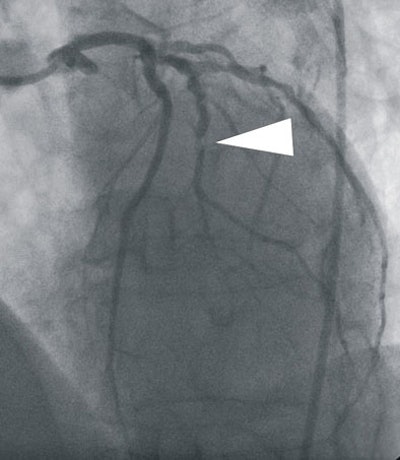

| In a 64-year-old man presenting with chest pain, 3D and multiplanar reconstructions of coronary CTA images show a significant stenosis in the first diagonal branch of the left anterior descending (LAD) artery and a 70% stenosis in the mid right circumflex artery (RCA) (arrows). All images courtesy of Dr. Balázs Ruzsics, Ph.D., and Dr. U. Joseph Schoepf. |

The coronary CTA results revealed significant coronary artery stenosis (> 50%) in 16 of the 35 patients. Compared to conventional catheter-based angiography, coronary CTA had sensitivity of 98%, specificity of 88%, and accuracy of 92% for detecting coronary artery stenosis.